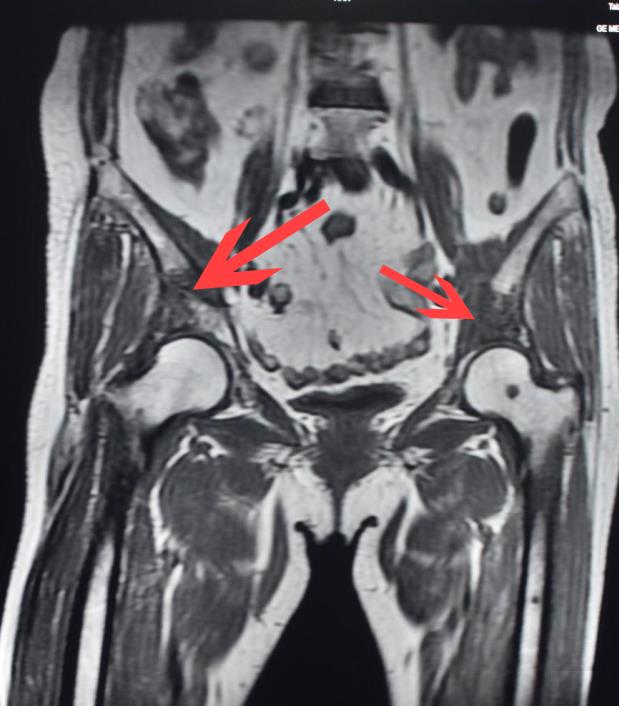

70岁的方女士(化名)家住路桥,平日身体一直很好。最近半年来,她总感觉胸口有点闷闷的,以为自己上了年纪,便没有理会,也没有接受其他治疗。最近几周,老人开始感觉髋关节经常酸酸的,双脚走路时常常发软,心想着肯定是前段时间锻炼走路走多了,脚酸了,便缩短了体育锻炼的时间。然而,前几天,方女士感到骨头都开始刺痛难忍了,方女士被家人送到台州市博爱医院疼痛科就诊。接诊的疼痛科主任医师王军会专业院长在检查后发现,在患者的双侧髋臼、髂骨都能看到溶骨性骨质破坏,其中髋关节部分骨头“消失”了!

方女士十分不解,“骨头怎么化了,难不成身体里长了虫子,虫子把骨头吃掉了?”在随后的腰椎检查中,医生发现,不仅髋关节发生病理性溶骨,腰骶椎等区域也都有骨质破坏,结合肺部CT检查,经会诊,确诊老人是患上了肺癌,是癌细胞“吃”掉了骨头。